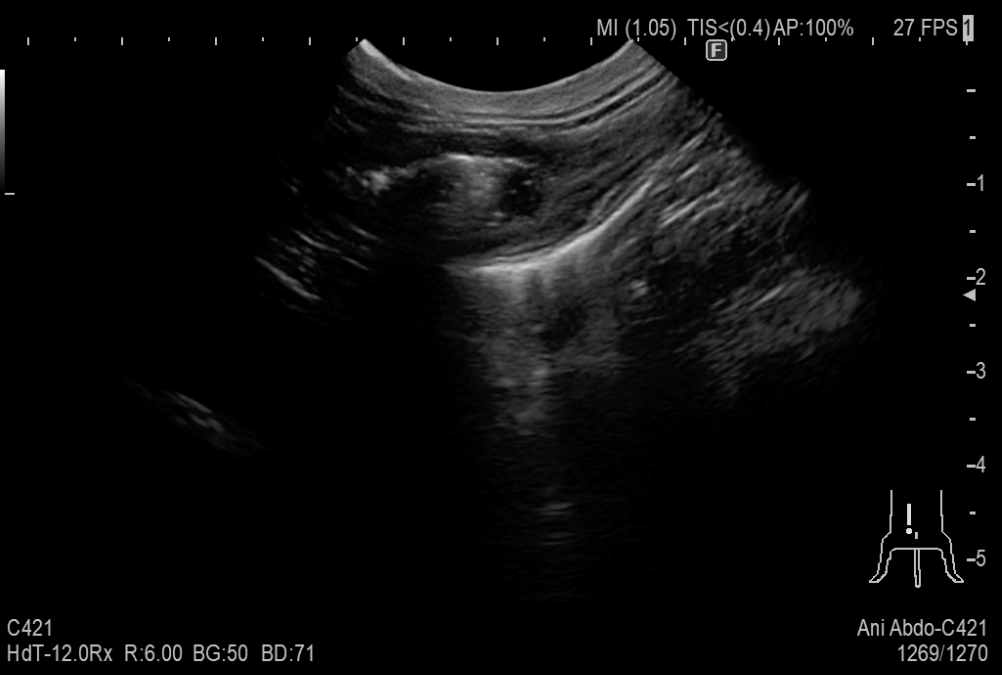

嘔吐を繰り返している8歳の猫が来院しました。

超音波検査にて消化管に腫瘍らしきできものが認められたため摘出を行いました。腹水が認められ、腹水の成分から腹腔内に炎症があることが分かりました。